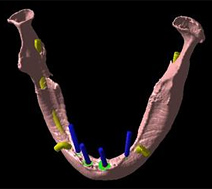

実際にCTで撮影し、「CTデータ3D立体構築画像変換検査」したものがどう見えるのがご覧下さい。CTデータ3D立体構築画像変換検査した場合、3次元でどこにどのようにインプラントを埋め込んでいけばいいのか、立体的に把握することができます。

CTデータ3D立体構築画像変換検査は患者さまの顎の骨や歯の状況を立体的に把握します。あらゆる角度から検討でき、インプラントの植え込み位置、角度などの事前シミュレーションが的確に行われ、数値化することができます。

この下記の写真は手術前に行う、3D立体画像構築画面です。

この患者さまの下顎の骨、そして神経が見えています。

この患者さまの下顎の骨、そして神経が見えています。

吉本歯科医院でインプラント治療を行う患者さまの顎の状態は、CT画像だけでなくここまで立体化されたものが手術前には手元にあり、シミュレーションを行ってから実際の手術に入るような流れをとっております。

さて、この写真、黄色くうにょうにょとしているのが神経です。

本来骨の厚みがある患者さまの場合は神経の黄色い部分は骨の中に隠れているため3D立体画像で真上から見た場合かくれて見えません。

この方の場合、骨が神経の出口(オトガイ孔)まで磨り減ったためにこのように写ります。